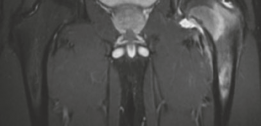

High-resolution, thin-slice computed tomography (CT) with multiplanar reconstruction is the gold standard for defining the osseous anatomy. The CT scan accurately delineates the nidus as a well-circumscribed, radiolucent focus, often containing a central fleck of mineralization, surrounded by varying degrees of sclerosis. The surgeon must meticulously map the location of the nidus relative to reliable arthroscopic landmarks, such as the medial synovial fold, the zona orbicularis, and the articular margin of the femoral head.

Magnetic resonance imaging (MRI) is highly sensitive for detecting the profound bone marrow edema and adjacent soft tissue inflammation characteristic of osteoid osteomas. While MRI may obscure the nidus itself due to the overwhelming edema signal, it is invaluable for assessing the extent of reactive synovitis, evaluating the integrity of the articular cartilage, and identifying concurrent labral pathology.